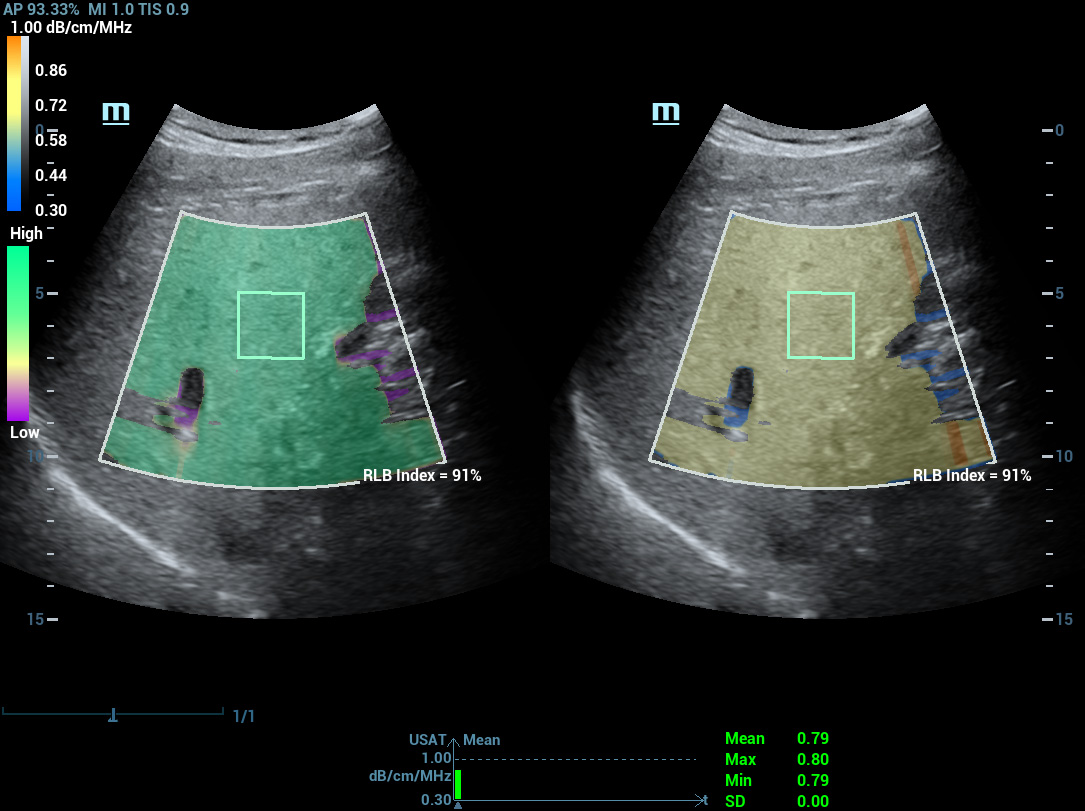

Analisi di laboratorio multiparametriche del fegato grasso

Le analisi di laboratorio multiparametriche del fegato grasso forniscono molteplici strumenti di analisi quantitativa basati su diverse tecnologie acustiche. Consentono di effettuare l'analisi quantitativa della steatosi e migliorano la sensibilitĂ della rilevazione del fegato grasso in fase precoce.